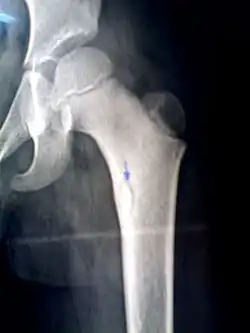

Sequestrum

A sequestrum (plural: sequestra) is a piece of dead bone[1] that has become separated during the process of necrosis from normal or sound bone.

It is a complication (sequela) of osteomyelitis. The pathological process is as follows:

The sequestra are surrounded by sclerotic bone which is relatively avascular (without a blood supply). Within the bone itself, the haversian canals become blocked with scar tissue, and the bone becomes surrounded by thickened periosteum.